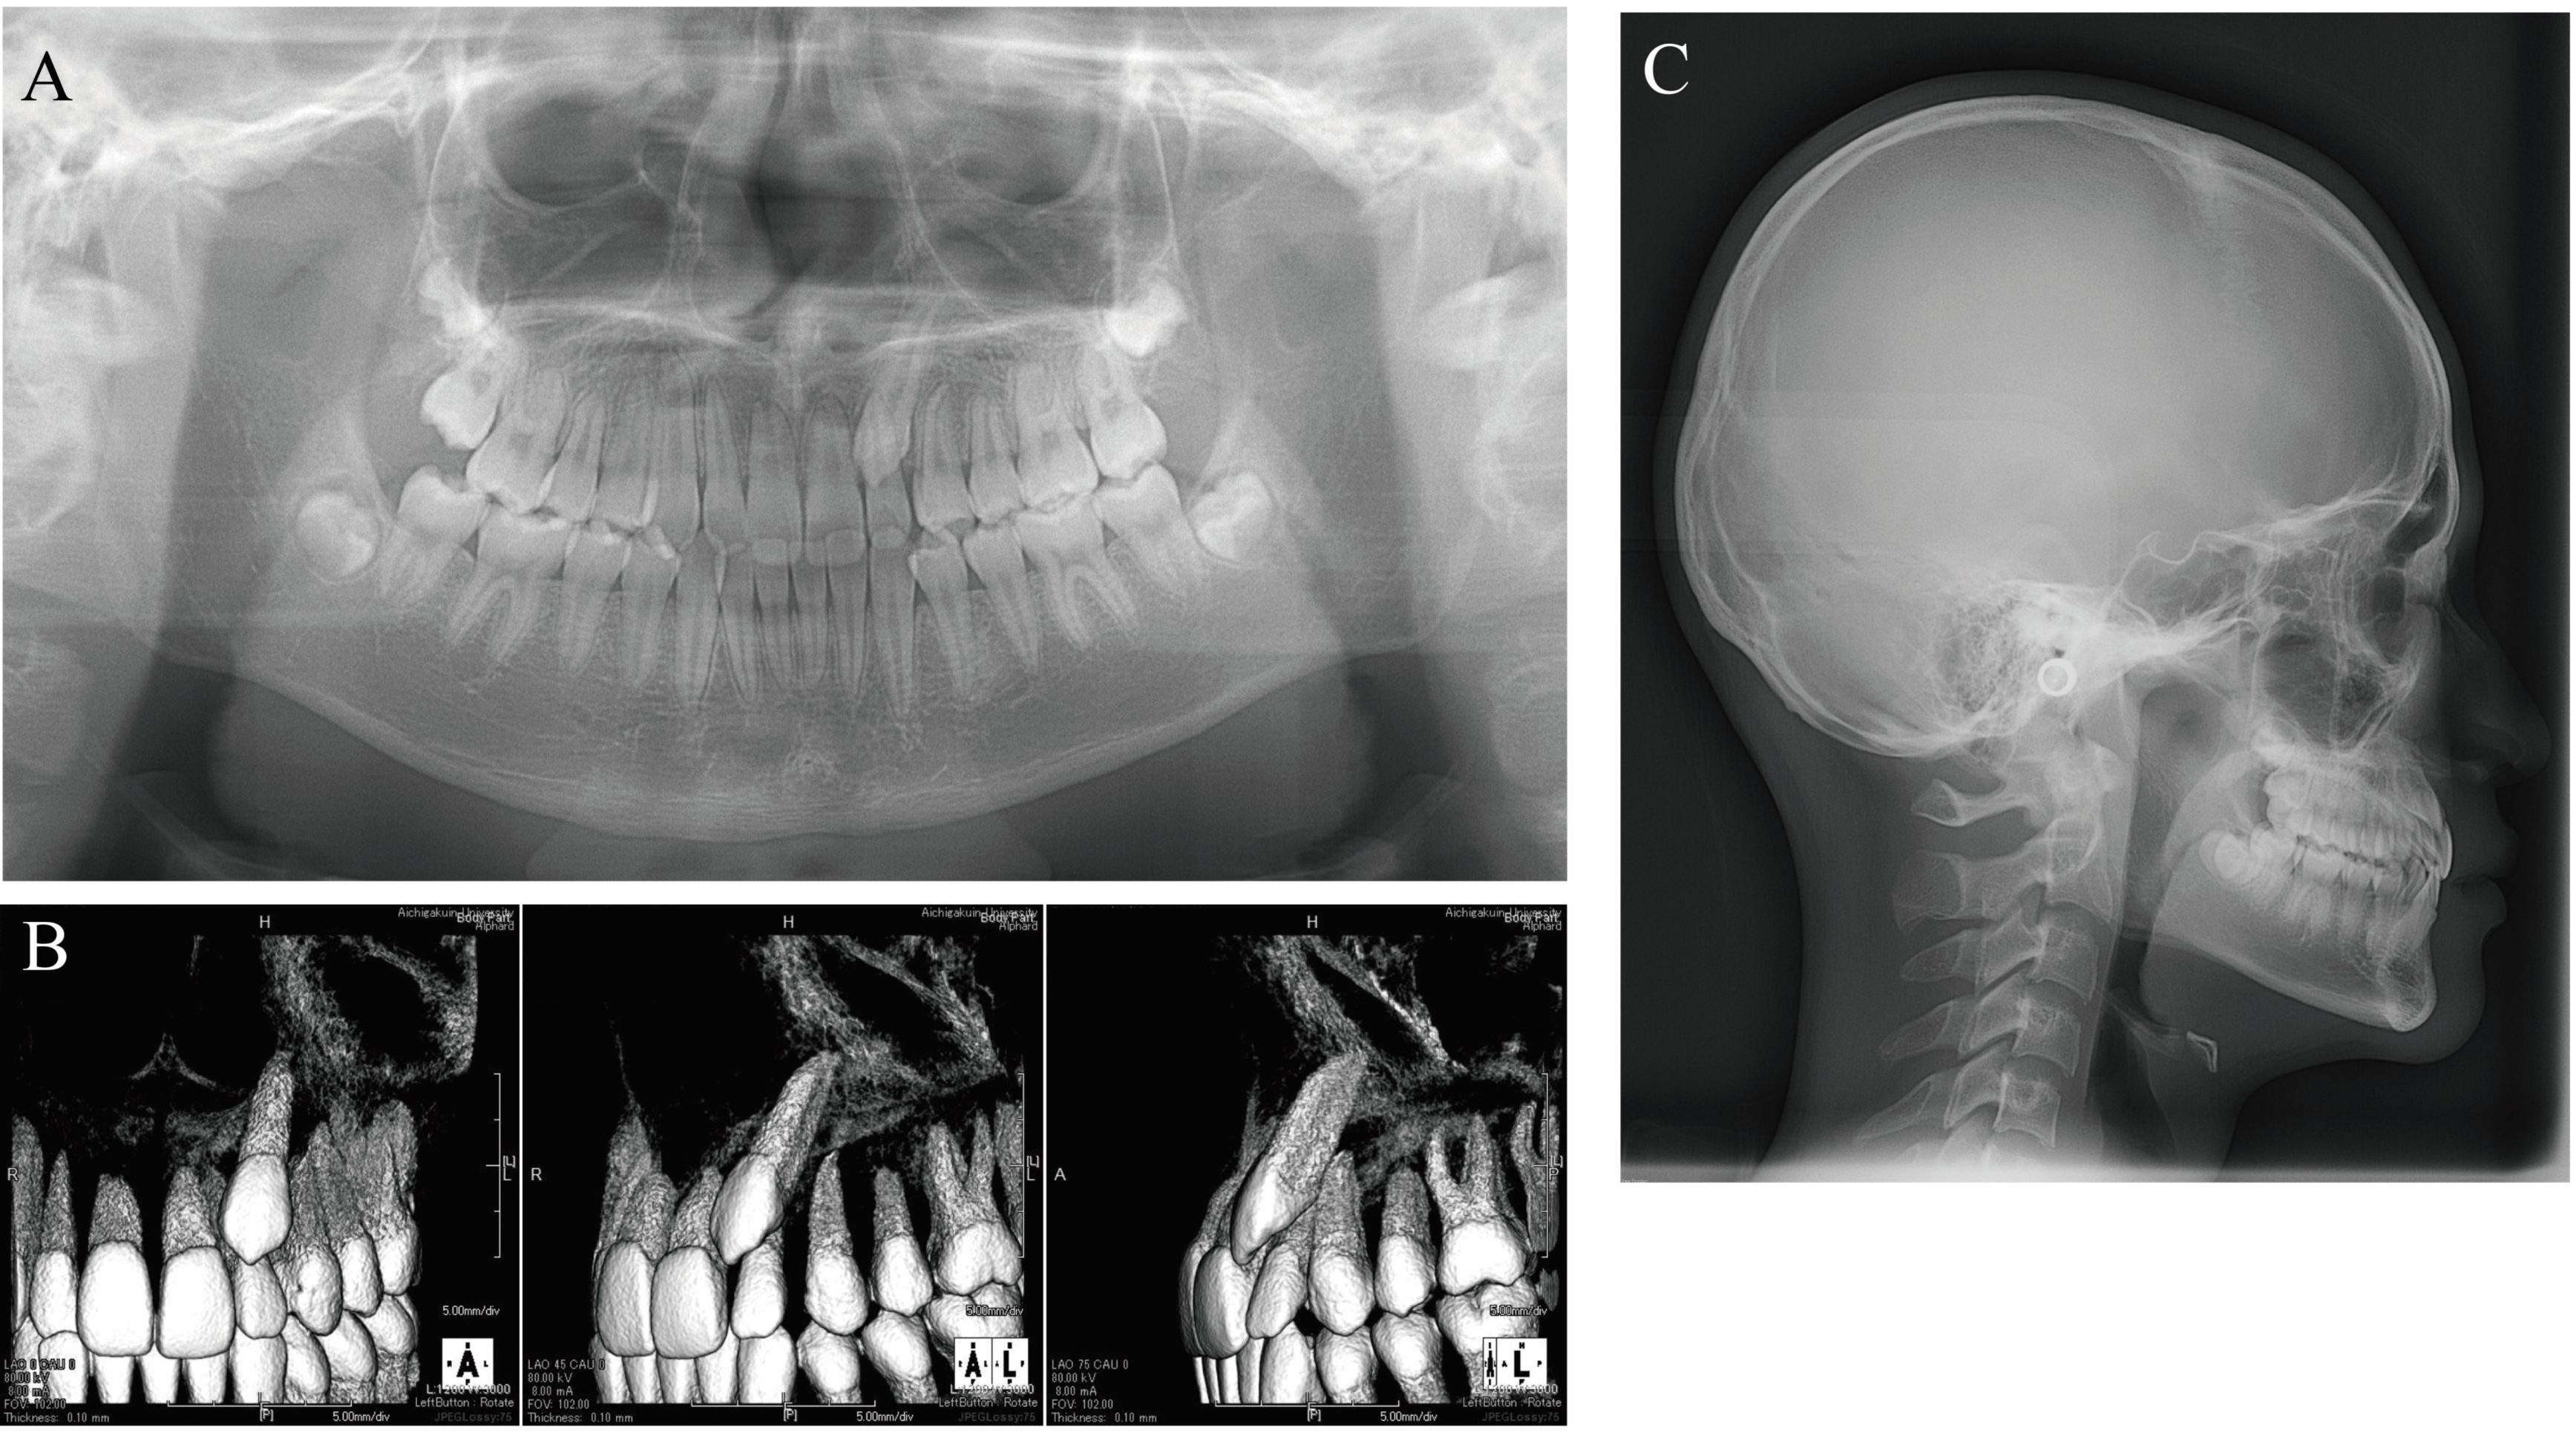

Panoramic X-ray and cone-beam computed tomography (CBCT) images showed that the maxillary left canine had erupted ectopically due to eruption disturbance. The maxillary left canine was mesially inclined with its crown near the labial root surface of the lateral incisor. The cusp of the canine was positioned more mesially than the lateral incisor axis. There was no evidence of canine contact with the lateral incisor or root resorption of the adjacent permanent teeth. There was no abnormality in the number of teeth. Tooth germs of the maxillary and mandibular right and left third molars were observed; the tooth germ of the maxillary left third molar was almost as large as the ipsilateral first and second molars.

Lateral cephalometric radiography showed no discordance in the anteroposterior position of the maxilla and mandible, with SNA of 90.5°, SNB of 88.5°, and ANB of 2.0°. Vertically, the patient had a low Frankfort-mandibular plane angle (FMA) of 14.0°. U-1 to NA was 2.0 mm/14.0°, indicating that the axis of the maxillary central incisor was normal, but that it was lingually positioned. L-1 to NB was 2.0 mm/14.5° and the FMIA was 80.5°, indicating that the mandibular central incisor was inclined and positioned lingually. The resulting interincisal angle was 150.0°, a large value exceeding 2SD (Figure 3).

The mesiodistal positions and axial inclination angles of the maxillary first molars were also measured (Figure 4). Mesiodistal measurements were as follows: A′-ptm′ 51.0 mm, A′-Ms 32.5 mm for the right and 28.0 mm for the left, and ptm′-Ms 18.5 mm for the right and 23.0 mm for the left (the left one was approximately 4.5 mm more mesial than the right one). As described by Byloff et al. [16] and Mayara et al. [17], the line connecting the midpoint of the occlusal surface of the maxillary first molars and the midpoint of the mesial and distal root apexes was defined as the maxillary first molar axis (Mp), and the angle between the palatal plane and the maxillary first molar axis was defined as the maxillary first molar axial inclination angle (α). The inclination angle was 83.0° on the right and 88.0° on the left, indicating that the more mesially located left maxillary first molar was more mesially inclined (Table 1).

Figure 3. Initial radiographs. (A) Panoramic radiograph. (B) Cone-beam computed tomography. (C) Lateral cephalogram (age, 14 years 4 months).